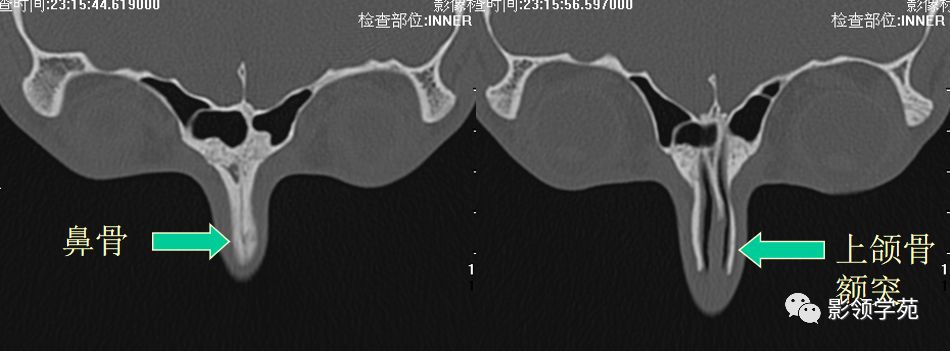

鼻骨正常侧位

鼻骨横断面HRCT

鼻骨冠状面HRCT